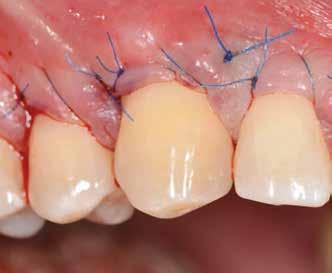

Az eljárást helyi érzéstelenítés mellett végeztük (4%-os articaine-hidroklorid 1:100 000 adrenalinnal). Papillakímélő, U alakú palatális bemetszést végeztünk, teljes vastagságú nyálkahártyalebeny preparálás történt, a lebenyt bukkálisan feltekertük (5. ábra). A lebeny bukkálisan feltekert részén de-epitelizációt végeztük el, amellyel kompenzálni tudtuk a bukkális lágyszöveti defektust. Szakaszos előfúrást végeztünk, és a bredent copaSKY 4x10 implantátumot 30 Ncm behajtási nyomatékkal helyeztük be (6. ábra). Az implantátumot 1 mm-re szubkresztálisan helyeztük be, hogy később szélesebb emergenciaprofilt tudjunk kialakítani (7. ábra). Az egyedi ínyformázó úgy készült, hogy kompozitot vittünk fel a titánbázisra, és így formáztuk a lágyszöveteket a transzgingivális gyógyulási fázis során (8. ábra). Az egyéni ínyformázó tulipán formájú, hogy kialakítsa a kívánt emergenciaprofilt. A lágyszövetet feszülésmentesen zártuk #6/0 nem felszívódó, monofil fonallal (Optilene, B. Braun Deutschland; 9. a–b. ábra). Posztoperatív röntgenfelvétel készült, ami alapján az implantátum a szomszédos fogakkal párhuzamos elhelyezést mutatott (10. ábra). Posztoperatív utasításokat adtunk a páciensnek a műtéti terület körüli szájhigiénia fenntartása érdekében. A beavatkozást követő egy héttel a varratokat eltávolítottuk, és a kezelt terület kielégítő gyógyulást mutatott (11. ábra). A 4 hónap utáni késleltetett terhelést a páciens kívánsága szerint terveztük.

8. ábra: Egyéni ínyformázó titánbázison, tulipán alakú emergenciaprofillal. — 9. a. ábra: A sebzárás okkluzális nézete.